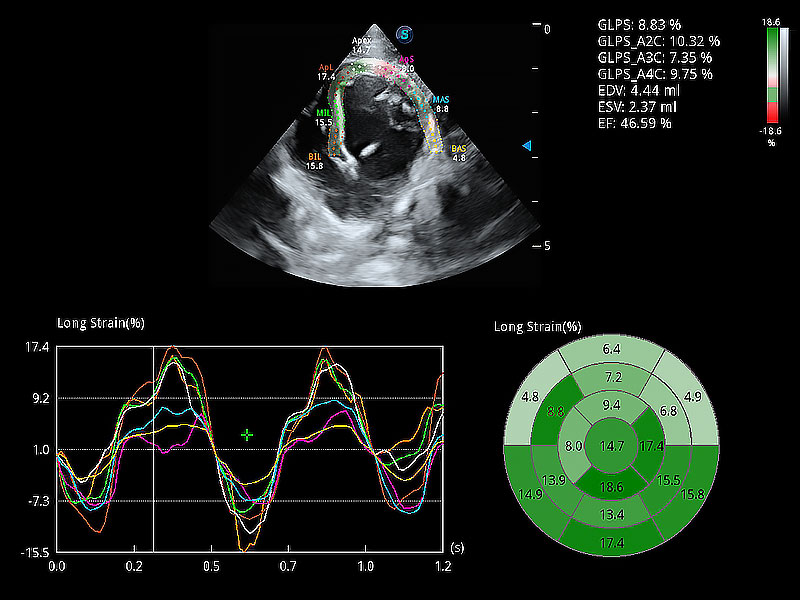

通过心肌识别技术与二维斑点追踪技术相结合,对心脏的超声图像进行量化分析。计算心肌17个节段的应变、应变率、速度、位移等,并通过牛眼图的形式进行呈现。

能够基于左心室壁追踪和辛普森法,自动计算射血分数,支持多个可移动点描迹,与手动测量相比,极大节省了动物医生的时间和精力。